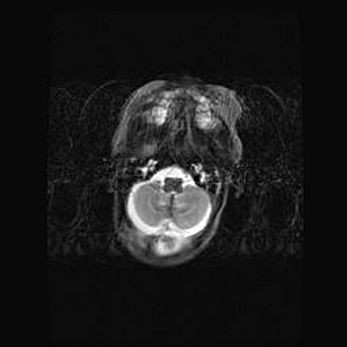

Церебральная ишемия II.

Возраст: 5 дней

Вес: 3400 г

Пол: женский

Окружность головы: 35 см

Срок гестации: 39 недель

Церебральная ишемия – это заболевание, характеризующееся недостаточностью (гипоксией) либо полным прекращением (аноксией) снабжения мозга кислородом по причине закупорки одного или нескольких сосудов. Это приводит к  что метаболическим расстройствам различной степени тяжести в тканях головного мозга, развитию коагуляционных некрозов и гибели нейронов.